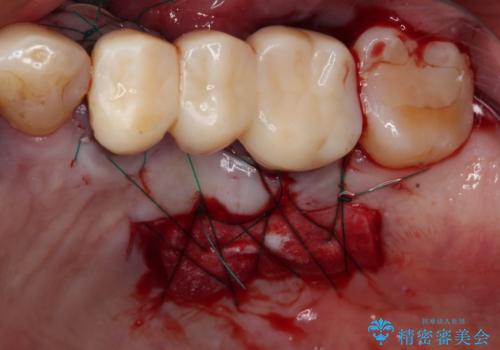

抜歯後、骨吸収量が多く、歯肉のラインが不揃いとなっているため骨造成術を、硬い歯肉が失われて清掃性が低下するため角化歯肉の移植術を行い、また並行して支台歯の根管治療を行っていき、環境を整えた上でオールセラミックブリッジにて補綴治療を行うこととしました。